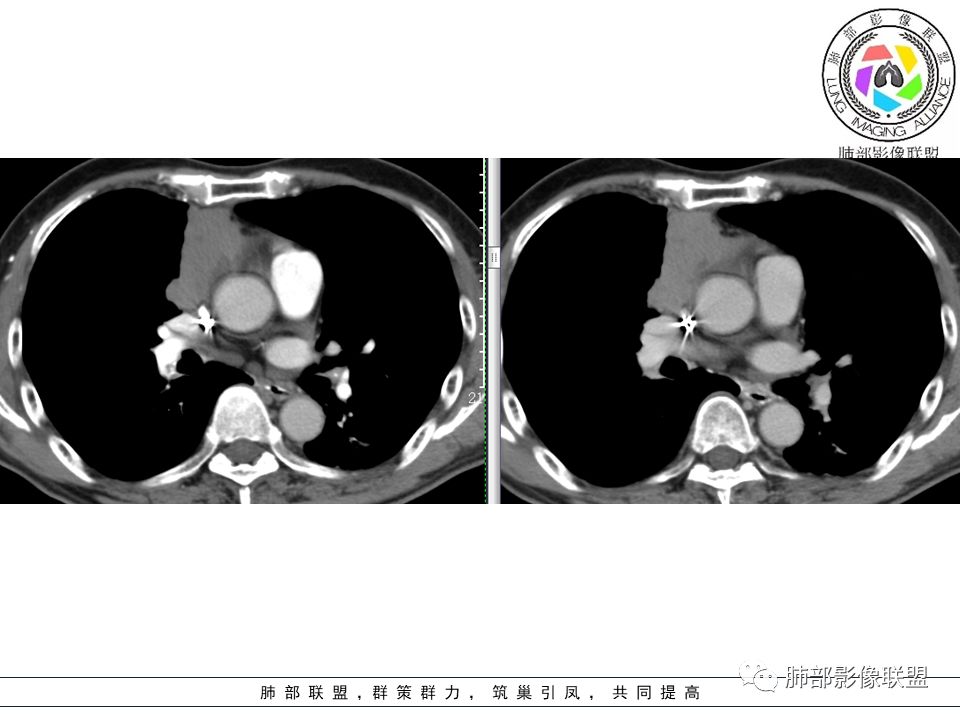

前纵隔分叶状软组织团块,包绕血管,周围脂肪间隙消失,其内可见钙化,增强扫描轻中度强化。首先考虑侵袭性胸腺瘤,不除外纵隔型肺癌。

胸腺上皮性肿瘤包括胸腺瘤和胸腺癌,而前者是前纵隔最常见的肿瘤;现目前多采用1999年WHO胸腺肿瘤组织学分型,按病理类型可分为6个亚型,即A、AB、B1、B2、B3及胸腺癌,又根据肿瘤的侵袭性和复发性将胸腺瘤分为低危型胸腺瘤(A、AB、B1)、高危型胸腺瘤(B2、B3)和胸腺癌;“良性胸腺瘤”的概念不符合医学实践,即使A型胸腺瘤也存在复发和转移的风险,所以现在胸腺瘤均为恶性肿瘤,都具有潜在复发和转移可能,只是恶性程度不一。

因为有时候影像不好鉴别胸腺瘤的亚型,尤其少数B3型跟胸腺癌鉴别仍存在困难;那如何大致辨别低危型胸腺瘤、高危型胸腺瘤跟胸腺癌呢?我们主要从肿瘤的轮廓形态、肿瘤内部的成份(囊变坏死、钙化、纤维分隔等)、周围组织侵犯情况(胸膜、血管、心包、肺、膈神经)、有无纵隔淋巴结转移及远处转移来综合分析,为疾病的治疗及预后是有重要价值的。

胸腺瘤/胸腺癌的影像分析

1.轮廓形态:

包膜完整、边缘光滑、规则---低位胸腺瘤;

边界不清、边缘不规则、分叶---高危胸腺瘤和胸膜癌;

2.内部成分:

a.多数密度均匀,少见囊变坏死,见纤维分隔影及钙化---多见于低位胸腺瘤,而且纤维分隔影以AB型显著, 实质性钙化多提示AB型及以上,A型钙化多发生于被膜钙化,呈蛋壳样;

b.密度不均匀,囊变坏死多见,纤维分隔影少见,有钙化---多见于高危胸腺瘤及胸腺癌以上,尤其大片囊变坏死多见于B1型以上胸腺瘤跟胸腺癌;钙化多见于肿瘤实质内,非边缘区,多发的泥沙样、微钙化及多形性钙化多见于B2、B3型;

(随着侵袭性的增强,纤维分隔影会逐渐减少)

3.周围及远处情况:

a. 纵隔脂肪线清晰,无胸膜、血管、心包及肺情况,罕见纵隔淋巴结肿大及远处血行转移--低危胸腺瘤

b. ①纵隔脂肪间隙模糊、胸膜、心包侵犯、膈肌受累--见于高危胸腺瘤及胸腺癌,但是心包侵犯多见于B3胸腺瘤跟胸腺癌

②纵隔大血管侵犯、肺转移、膈神经麻痹、淋巴结转移及远处血行转移---多见于胸腺癌,B3胸腺瘤罕见